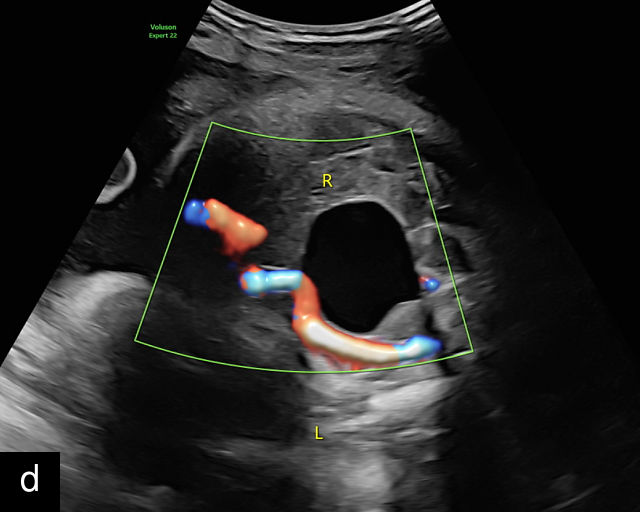

The umbilical cord serves as the lifeline connecting the fetus to the placenta. It arises from the midportion of the fetal abdomen and typically inserts into the center of the placenta (Figure 16). The average length of the umbilical cord is approximately 55 cm (22 inches).185 It contains three vessels: two arteries, which originate from the fetal left and right internal iliac arteries, and one vein, collectively referred to as a three-vessel cord.

16

Normal appearance of the umbilical cord with two umbilical arteries and a single vein. (a–c) Cross-section of the umbilical cord on grayscale (a,b) and power Doppler (c) ultrasound. In the normal cord, three vessels are visible: a larger umbilical vein and two smaller umbilical arteries. This characteristic appearance is often referred to as the 'Mickey Mouse' sign, the larger circle (umbilical vein) representing Mickey’s face while the smaller circles (arteries) form his ears. (d–g) Grayscale (d) and color Doppler (e–g) images of transverse section of the lower fetal abdomen showing the two umbilical arteries diverging around the fetal bladder. (h) Longitudinal ultrasound view with color Doppler of a normal umbilical cord showing three vessels present in each coil: two arteries with flow in one direction and a single vein with flow in the opposite direction.

The umbilical vein carries oxygenated blood from the placenta to the fetus, while the two umbilical arteries return deoxygenated blood and waste products from the fetus to the placenta for exchange with the maternal circulation. These vessels are surrounded and protected by Wharton’s jelly, a specialized connective tissue derived from the extraembryonic mesoblast, which cushions the vessels and prevents compression. As the umbilical cord approaches its placental insertion, the two arteries form Hyrtl’s anastomosis, a connection that helps equalize blood flow between the arteries.

At a minimum, the mid-trimester ultrasound should include identification and documentation of the umbilical cord's fetal and placental insertions, as well as the number of cord vessels.66,186,187 In a transverse grayscale section of the cord, the two umbilical arteries can be visualized alongside the larger, thinner-walled umbilical vein, creating a characteristic ‘Mickey Mouse’ appearance (Figure 16a–c). Additionally, in a transverse section of the lower fetal abdomen, the umbilical arteries are seen encircling the fetal bladder. This can be seen on grayscale ultrasound and confirmed with color flow Doppler (Figure 16d–g).